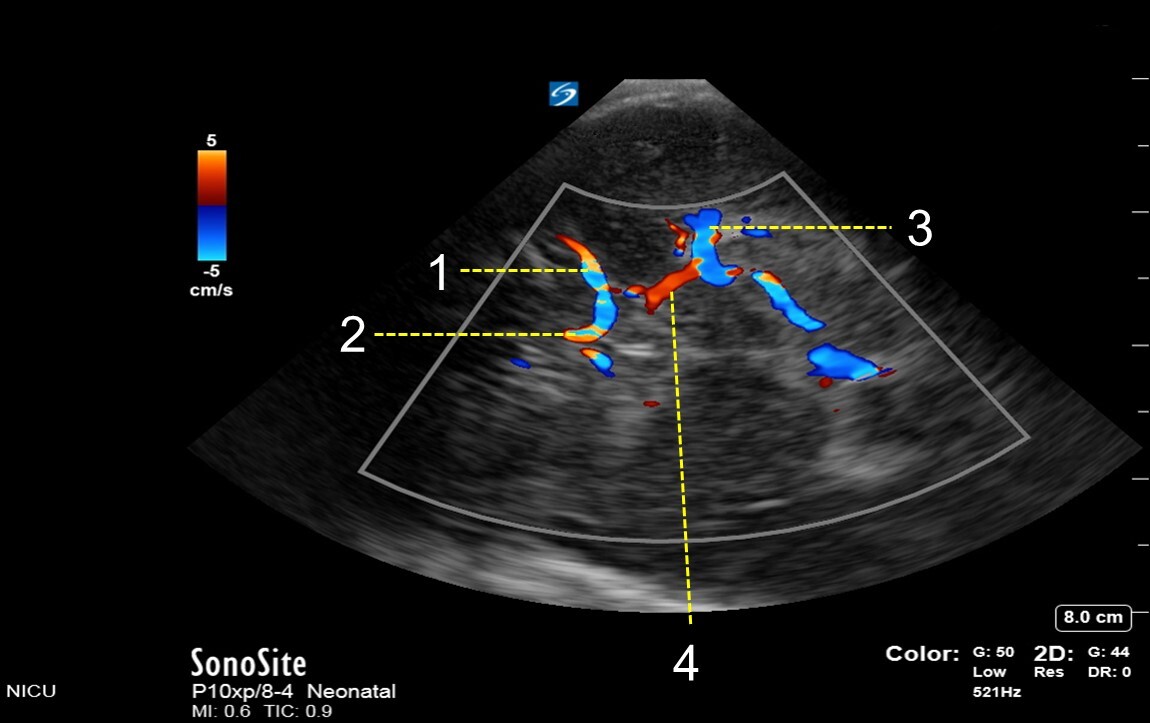

Neonatology Temporal Bone Transverse Basal View Image

1. Middle Cerebral Artery (MCA)

2. Anterior Cerebral Artery (ACA)

3. Posterior Cerebral Artery (PCA)

4. Posterior Communicating Artery (PCOM)